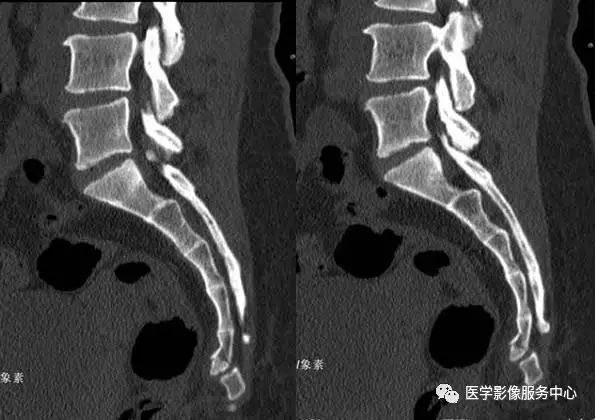

附病例(X线+CT):

病人女性,外伤后骶尾部疼痛,dr片示骶尾关节对应关系差,骶5椎体欠规则。ct重建示骶5椎体粉碎性骨折!

CT: